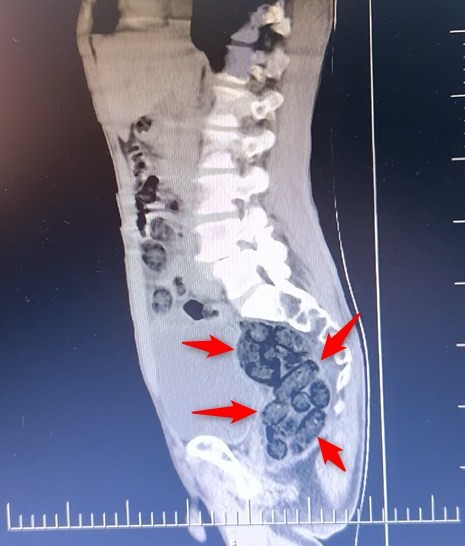

Durumundan şüphelenilen yabancı uyruklu bir yolcu üzerinde arama yapıldı. Yapılan incelemeler sonucunda yabancı uyruklu şahsın midesinde 64 Parça halinde toplam 472 gram uyuşturucu maddesi metamfetamin olduğu belirlendi.

Gözaltına alınan şahsın midesindeki uyuşturucu madde çıkartıldı. Emniyetteki işlemlerinin ardından adliye sevk edilen şahıs, çıkarıldığı mahkemece tutuklanarak cezaevine gönderildi.